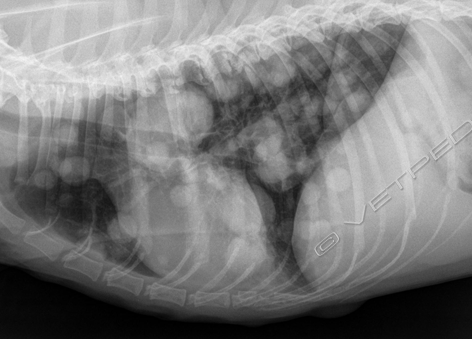

L’esame radiografico di norma si può eseguire senza sedazione; si può eventualmente eseguire una breve anestesia gassosa con induzione diretta. Viste le dimensioni della cavia, conviene eseguire di routine le proiezioni laterale e ventrodorsale di tutto il corpo, a meno che l’animale non sia gravemente debilitato e manovre stressanti poss...